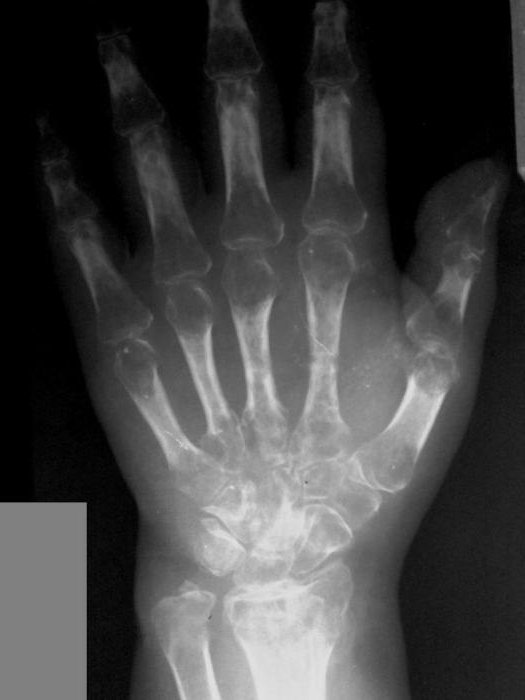

- рентгенографию — метод, позволяющий выявить изменения в костных и хрящевых тканях, связанные с остеопорозом;